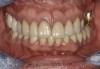

Fig 7. Existing dentition was sound periodontally and reasonably esthetic.

Figure 7